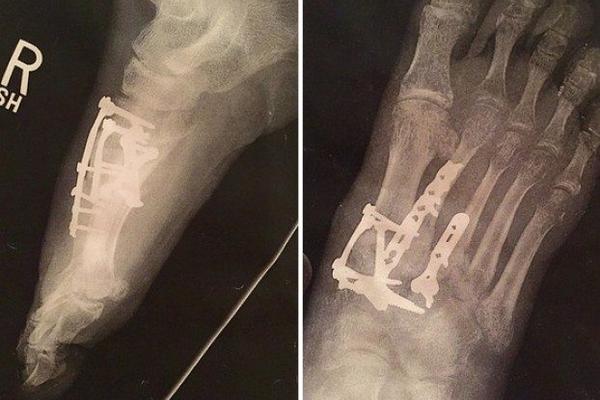

stopalo je počelo da menja boje

TRPEO JE NEZAMISLIV BOL U NOZI: Stopalo je prvo promenilo boju, a onda iz kože ISKOČILO OVO! Da se naježiš! (FOTO)